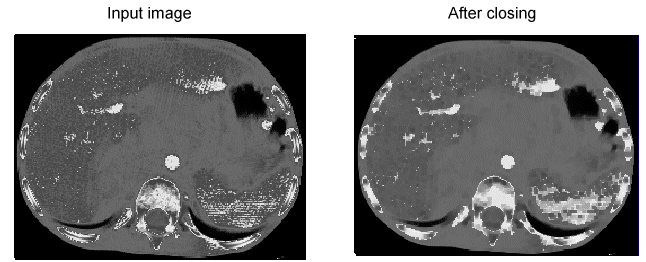

Closing

A closing operation first performs a dilation on the input image and then performs an erosion on the result in order to generate the output image. Closing an image reduces or completely removes dark areas of the image:

Image Processing Morphology Theory Grey Scale Morphology Closing

Both opening and closing operators tend to preserve the size and shape of large features while affecting the size and shape of small features.